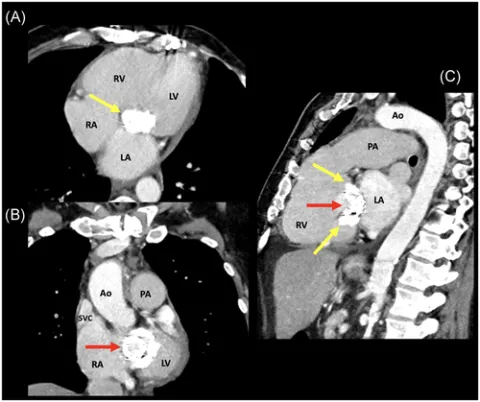

Transcatheter "valve-in-valve" mitral valve replacement for patient-prosthesis mismatch: Chronicle of a death foretold

Marin-Cuartas M, Noack T, Kiefer P, Borger MA. Transcatheter "valve-in-valve" mitral valve replacement for patient-prosthesis mismatch: Chronicle of a death foretold. J Card Surg. 2020 Dec;35(12):3606-3609. doi: 10.1111/jocs.15050. Epub 2020 Sep 28. PMID: 32985707.